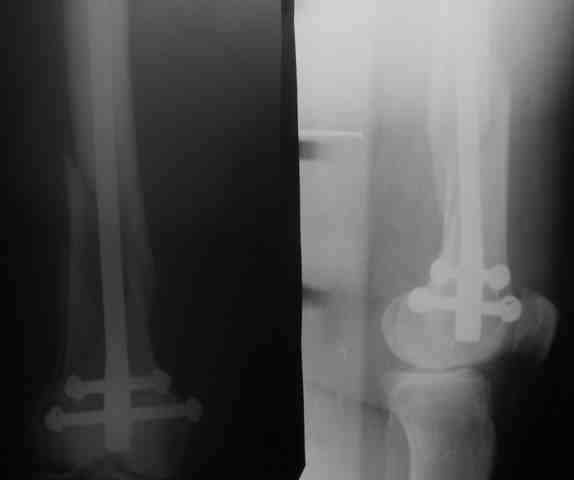

Рг в приложении.

Снимки вполне симпатичные. Единственное, по ротации не понял, уж больно неразборчивый тот, который без гвоздя.